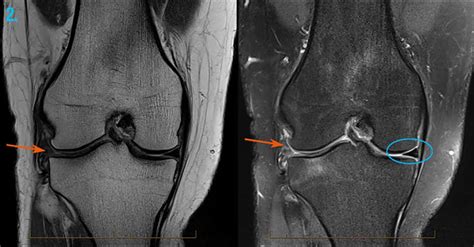

Knee Injury MRI